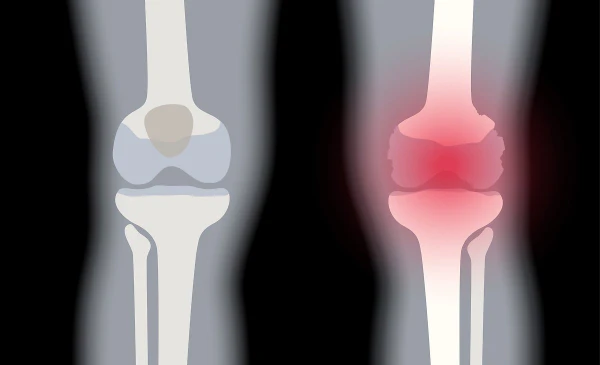

통풍이란 요산이 체내에 쌓여 관절에 염증을 일으키는 질병으로, 관절이 혹처럼 튀어나와 보일 정도로 심한 증상을 유발한다. 통풍이라 불리는 이 질병은 고통스럽고 찌르는 통증을 동반하며, 바람이 불면 더욱 심해지는 것이 특징이다. 이러한 고통은 주로 밤이나 새벽에 나타나며, 급성인 경우 일주일에서 한 달 동안 지속될 수 있다. 만성적인 경우에는 요산배설촉진제를 사용하여 치료된다.

통풍은 주로 체내에 과다 축적된 요산으로 인해 발생합니다. 요산은 우리가 섭취하는 다양한 음식이 소화되어 최종적으로 대사된 후 혈액에 녹아 있다가 소변으로 배출되는 물질입니다. 일반적으로 혈액 내에서 요산은 정상 수준을 유지하며 배설됩니다. 그러나 통풍 환자는 혈액 내 요산이 과다하게 증가합니다. 이러한 과다 축적된 요산은 결정체로 변화하고, 이러한 결정체가 관절 내에 침착하여 염증을 일으킵니다.

통풍 환자는 대개 고요산혈증이라 불리는 혈액 내 요산이 정상치를 넘어선 상태를 가지고 있습니다. 그러나 고요산혈증이 있더라도 모든 고요산혈증 환자가 통풍 환자는 아니며, 무증상으로 고요산혈증인 사람이 더 많습니다. 통풍 관절염은 고요산혈증이 심하고 지속되는 경우에 발병할 가능성이 크며, 발병 확률은 기간이 길수록 높아집니다.